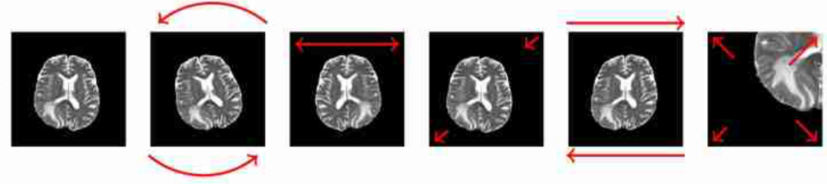

1. Geometric transformations and cropping

Geometric transformations include horizontal reflections, rotations, translations, shear, scaling, and random cropping. The parameters of these transformations can be either chosen manually or randomly sampled [1,4, 27]

Even though basic transformations have been proven to achieve good results in medical applications, care should be taken when applying them so as not to flip certain transverse images since organs are always on a certain side of the body or not applying high rotation angles as such an output is not possible in reality.